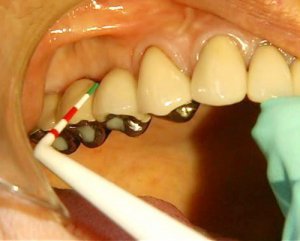

치주질환의 진행 정도는 가는 탐침(probing)을 치주낭에 깊이를 측정하는 방법으로 진단한다. 치주낭이 깊을수록 병증이 심각한 것이다. 서울대 치과병원 제공